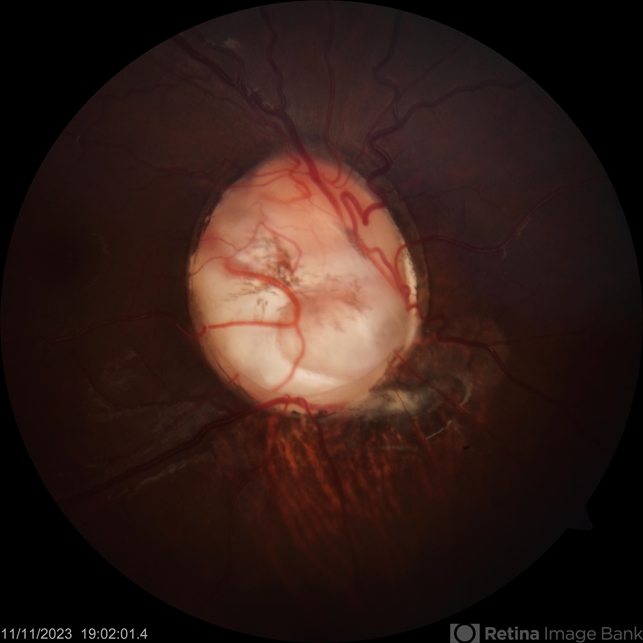

- disc coloboma

- A 17 year old male presented with diminution of vision in RE since childhood. On SLE anterior segment was within normal limits. Fundus showed coloboma of the disc.